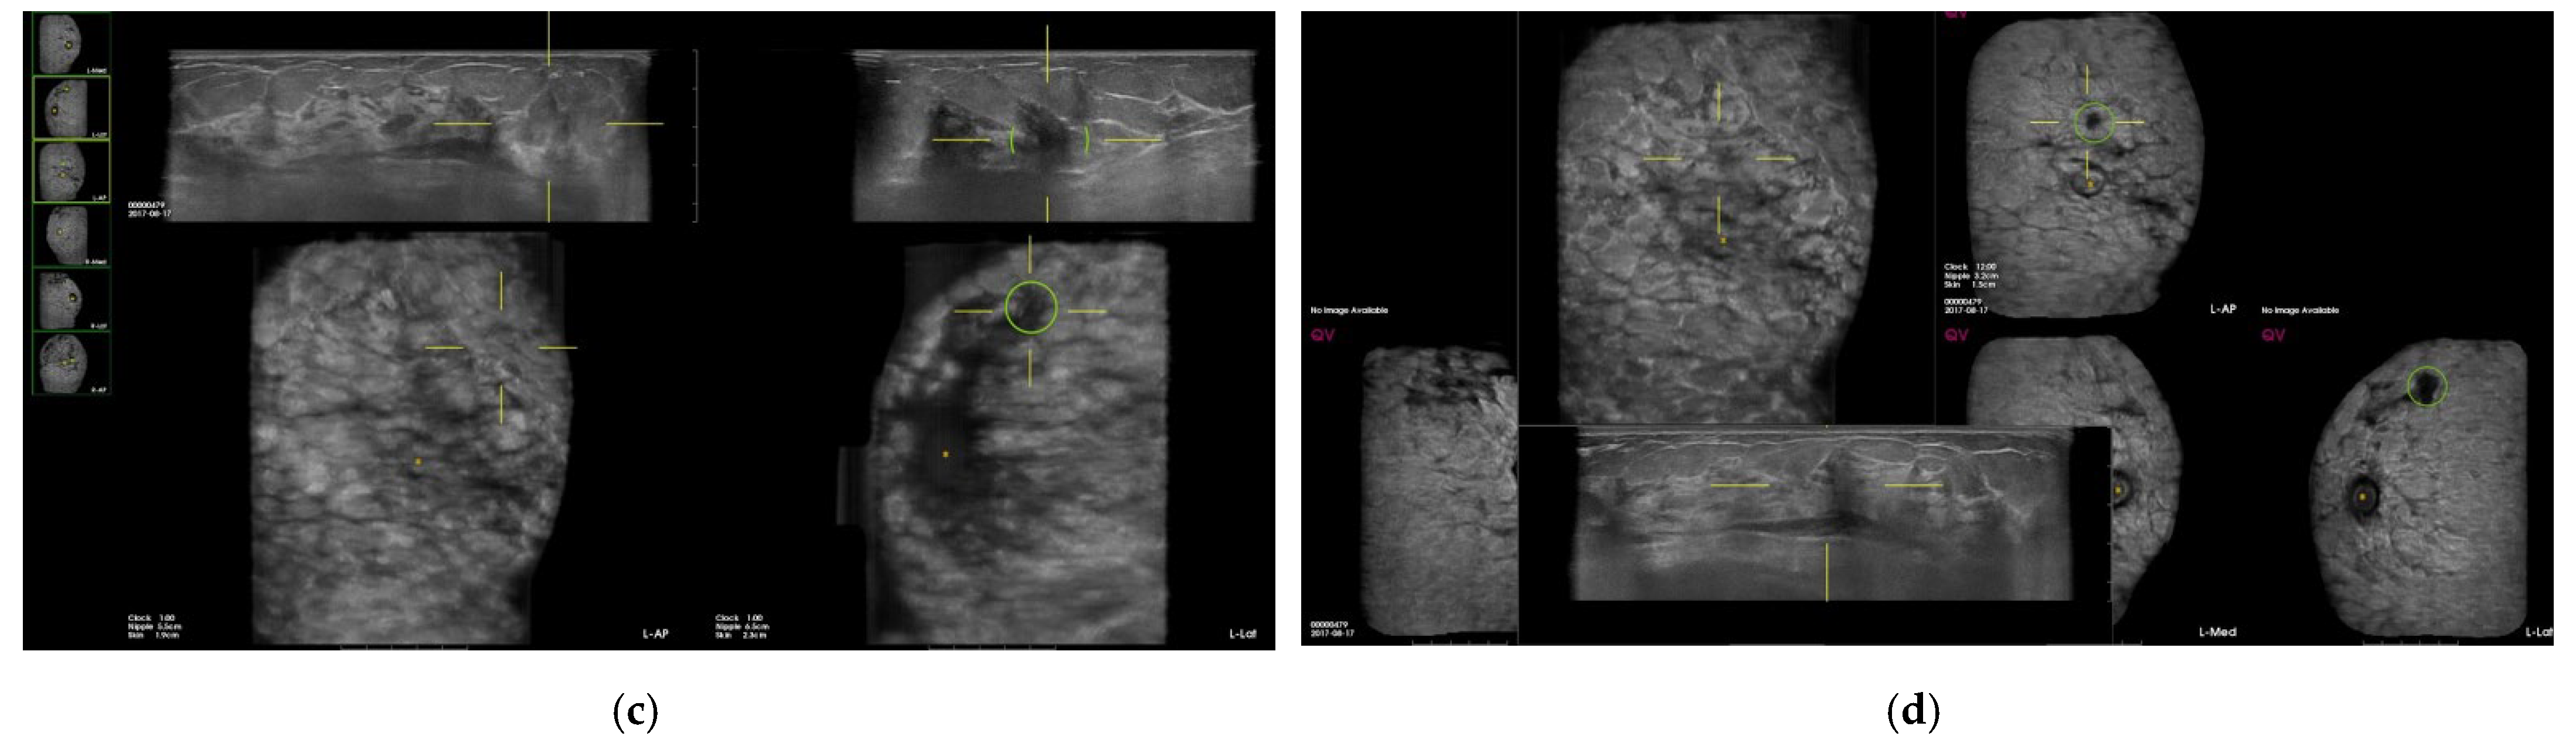

| Characteristics of CAD marks per lesion (n = 534) | n | % |

| Suspicious | 4 | 0.8 |

| Benign | 71 | 13.3 |

| Fat | 35 | 6.6 |

| Benign mass | 19 | 3.6 |

| Cyst | 9 | 1.7 |

| Fibrosis/heterogenous parenchyma | 8 | 1.5 |

| False-positive marks for pseudolesions | 459 | 86 |

| Marginal shadowing | 209 | 39.1 |

| Cooper’s ligament shadowing | 143 | 26.8 |

| Periareolar shadowing | 64 | 12 |

| Rib | 37 | 6.9 |

| Skin lesion | 6 | 1.1 |